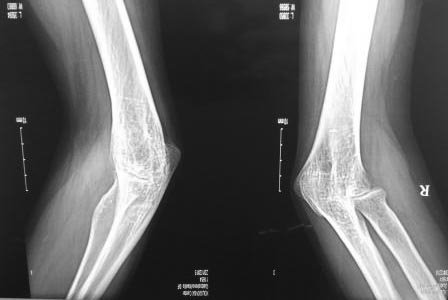

Анкилоз локтевого сустава |

Обратилась М.22г. В малолетнем возрасте получила травму локтевого сустава, лечилась у табиба. Теперь хочет выйти замуж, и просит помочь. Правая рука гипотрофична, движений в локтевом суставе нет. Можно ли делать артропластику, если да ,то где и какие нюансы? С уважением Абдурашид.